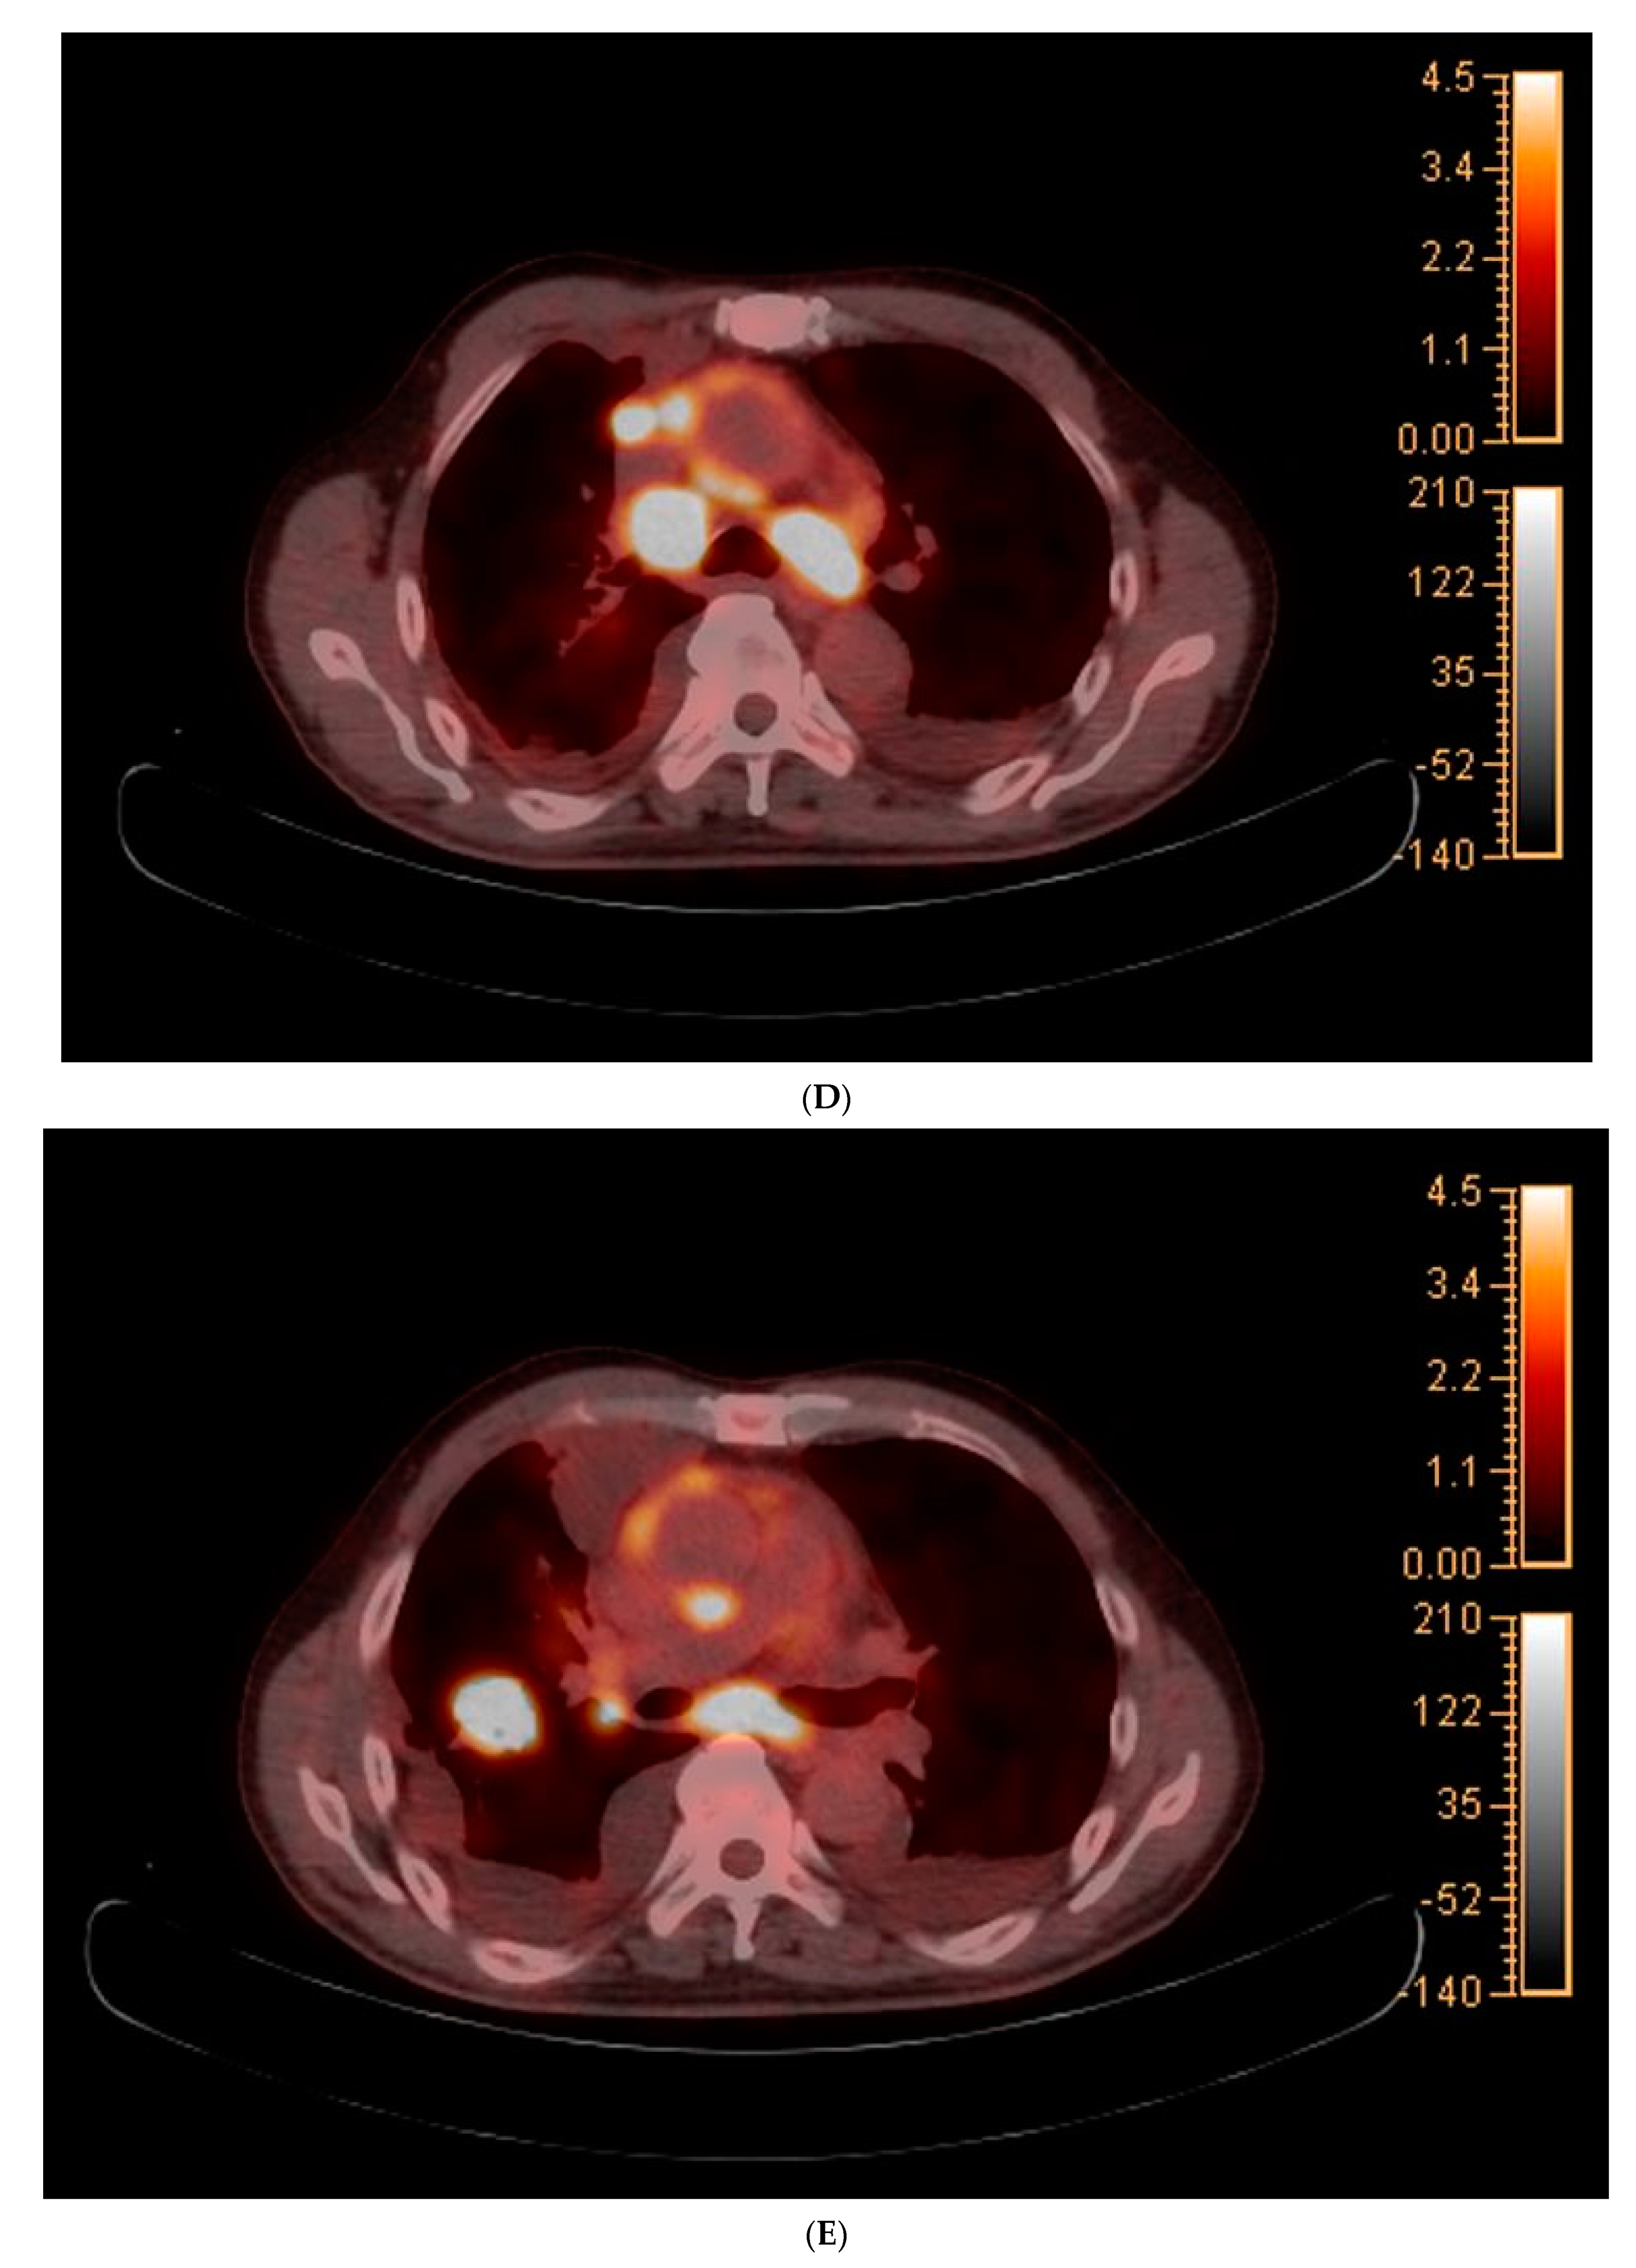

2. Case Report